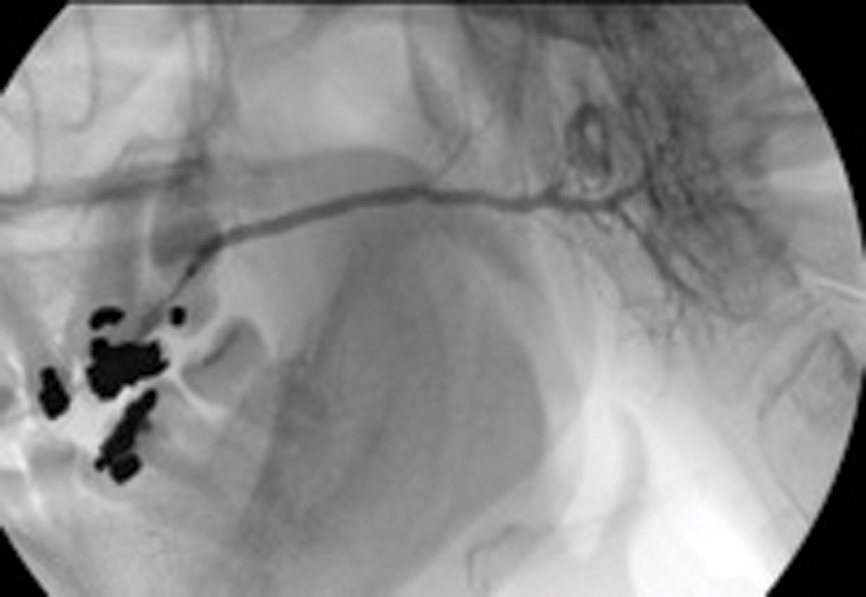

Figure 4: (A) Sialogram showing multiple stenoses located in the parotid duct before treatment.

Figure 4: (B) Appearance on sialogram following balloon dilatation.

Ductoplasty involves insertion of a fine angioplasty balloon using an on-the-wire-technique into the salivary duct, and manipulation of the balloon catheter through the duct stenosis. Again this is performed under radiological guidance and local anaesthesia. The balloon is inflated, the dilatation being maintained or repeated to eliminate any waisting in the balloon.

Our study has shown a 92% success rate in achieving balloon dilatation, with 82% demonstrating complete elimination of the stricture postoperatively [13].